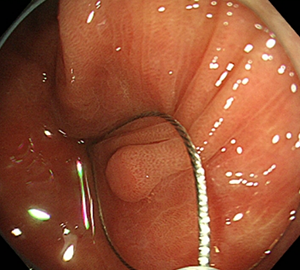

コールドスネアポリペクトミー(CSP)

合併症の非常に少ない優れた治療法であることから、近年大腸ポリープの外来切除法として急速に施行件数が増えてきています。当院ではこのコールドスネアポリペクトミーを主体としたポリープ切除を行っています。

| 1:ポリープを見つけます。 | 2:狭帯域光画像併用拡大観察で詳細に観察します。 | |

| 3:病変をスネアに通します。 | 4:周囲の正常粘膜をしっかり入れながら、病変を絞扼していき... | |

| 5:切除します。切除検体は吸引回収し病理検査を行います。 | 6:切除後に洗浄・観察して、病変の遺残ががないことを確認します。 |